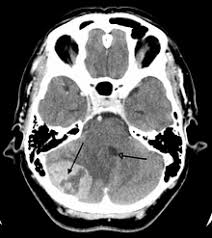

Early Signs Of Brain Cancer In Infants : What Every Parent Should Know About Cancer Early Warning Signs Of Cancer In Children 1 A Child Who Is Very Pale And Is Bleeding 2 A Child With Persistent Ppt Download : Vomiting that persists for more than 7 days and is worse when your child wakes up in the morning, wakes your child up at night, or is associated with a headache.. Home / general health / signs of brain tumor in children Persistent vomiting/feelings of nausea (over a two week period) can be a sign of a brain tumour. You will find out more about body changes and other things that can signal a problem that may need medical care. When brain cells grow abnormally or out of control, a tumor (a mass of cells) can form. Medulloblastomas are the most common type of childhood brain cancer.

Early Symptoms Of A Brain Tumor Mental And Physical Signs from i0.wp.com This is the most often dismissed symptom of brain cancer, just because it is so prevalent in daily life. Signs and symptoms will depend on the kind of tumor your child has, and where it is in the brain. New onset or change in pattern of headaches headaches that gradually become more frequent and more severe The signs and symptoms of a brain tumor vary greatly and depend on the brain tumor's size, location and rate of growth. Cancer occurs in people of all ages. Children of any age may be affected. The early signs of brain tumor in children may be as simple as headache and vomiting. Boys are affected slightly more often than girls.

Early diagnosis is important, particularly with solid tumours where, in most cases, treatment can be less intensive and more successful if the tumour is smaller and has not spread from the primary area at the time of diagnosis. Learn about the signs and symptoms of brain and spinal cord tumors in children. A brain tumor expert shares seven brain tumor symptoms to watch out for and advises on the best type of place to seek brain tumor treatment. But not all brain tumors cause headaches, and most headaches are not caused by tumors. When brain cells grow abnormally or out of control, a tumor (a mass of cells) can form. Headaches that get worse over time are a common symptom of brain tumors. The signs may vary according to the type, size, and location of the tumor or the age of the child. The children's hospital of philadelphia. Bone pain may cause the child to limp, refuse to walk, or become unable to walk. They are the second most common cancer in children, after childhood leukemias. Headache many children with a brain tumor experience headaches before their diagnosis. About 400 children in the uk develop brain tumours each year. Symptoms from pediatric brain tumors vary widely, depending upon the tumor's location and size.

Brain Tumors In Children 8 Warning Signs You Should Know Johns Hopkins Medicine from www.hopkinsmedicine.org The signs and symptoms of a brain tumor vary greatly and depend on the brain tumor's size, location and rate of growth. However, because they are so general, diagnosis can be difficult. A head that grows extremely fast a bulging, fuller soft spot (fontanel) on the head in babies changes in intellectual and/or physical abilities Therefore, as brain tumors develop and expand, they cause extra pressure in this closed space. You will find out more about body changes and other things that can signal a problem that may need medical care. Persistent vomiting/feelings of nausea (over a two week period) can be a sign of a brain tumour. Boys are affected slightly more often than girls. The most common kinds of cancer in infants include leukemia, brain tumors, neuroblastoma, and retinoblastoma.

Brain Tumors In Children Symptoms Diagnosis And Treatment from www.nationwidechildrens.org Cancers in children are sometimes hard to recognize because common illnesses or everyday bumps and bruises can mask the early warning signs. There are many other that affect children, including astrocytomas, gliomas, ependymomas, germinomas and more. This is the most often dismissed symptom of brain cancer, just because it is so prevalent in daily life. Ependymomas are a type of childhood brain tumor that can be benign (noncancerous) or malignant. Plus, learn the signs of brain metastases. Brain tumor in children pediatric brain tumors are masses of abnormal growth that occur in the brain or the in tissues and structures that are near to it. But not all brain tumors cause headaches, and most headaches are not caused by tumors. Still, cancer is the second leading cause of death in children younger than 15 years old, after accidents.

Cancer occurs in people of all ages. The most common brain tumor in children is medulloblastoma. Some of the more common symptoms of a brain tumor in children include: Plus, learn the signs of brain metastases. Too often you see someone fall, break a rib, go in to the doctor and discover a tumor.. The following article provides information about the various symptoms of this condition. Headaches, which may become more frequent and more severe feeling of increased pressure in the head unexplained nausea or vomiting Headache many children with a brain tumor experience headaches before their diagnosis. In some children, seizures are the first symptom of a brain tumor. Boys are affected slightly more often than girls. The signs and symptoms of a brain tumor vary greatly and depend on the brain tumor's size, location and rate of growth. Or, the cause of a symptom may be a different medical condition that is not a brain tumor. Babies with cancer can have many different symptoms, depending on what type of cancer it is.